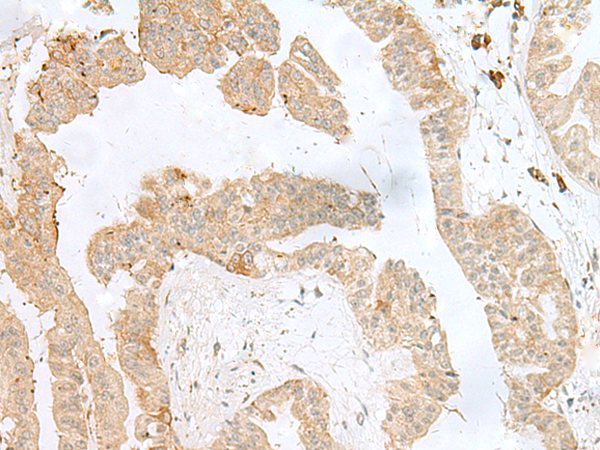

分类: 科研抗体货号: P02908别名: AGS3应用: WB,IHC反应种属: Human, Mouse, Rat